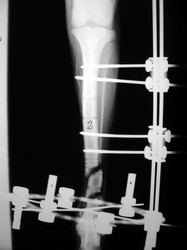

Fijación Externa

PRÁCTICAS CURSO DE FIJACIÓN EXTERNA PERFECCIONAMIENTO.

Híbrido.